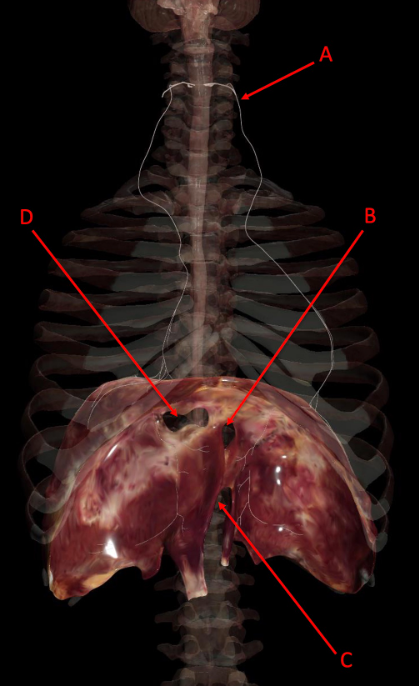

A

A. right middle lobe

B. left superior lobe

C. cardiac notch

D. left inferior lobe